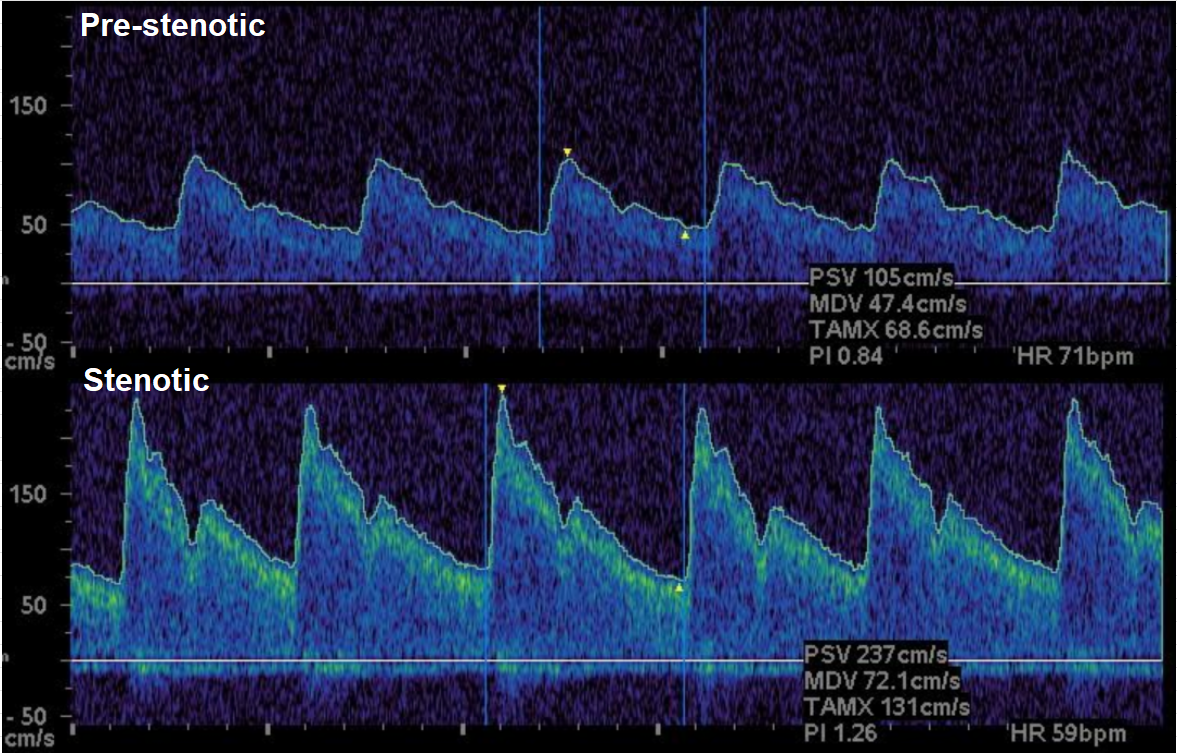

Screenshot 2025 06 02 at 1.53.45 pm

Screenshot 2025 06 02 at 1.54.04 pm

Screenshot 2025 06 02 at 1.54.22 pm